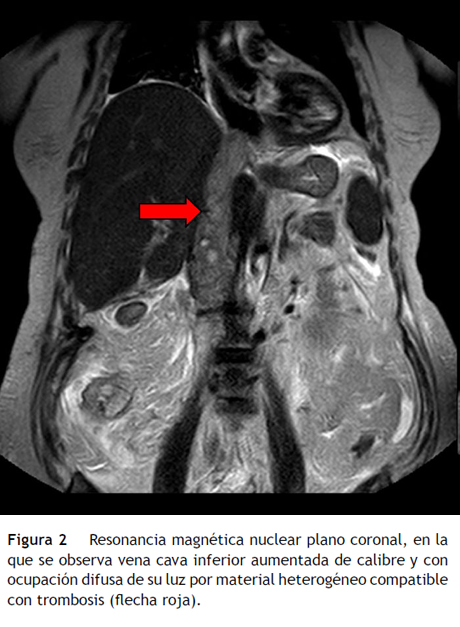

Caso

Mujer de 70 años de edad que se diagnosticó por tomografía computarizada (TC) abdominal de una masa renal derecha sugestiva de neoplasia con infiltración de la fascia de gerota sin evidencia de afectación adenopatía regional y asociada a trombo tumoral en vena cava inferior. Se realizó PET-TC con trazadores tumorales con elevación de características malignas en masa renal derecha e incremento metabólico en vena cava inferior atribuible a trombo de posible etiología tumoral, sin evidencia de enfermedad macroscópica en otras localizaciones. Se realizó nefrectomía radical y cavotomía con anatomía patológica de carcinoma de células renales papilar tipo 2 y trombo constituido por ese mismo tumor. Luego de tres meses, acudió por distensión abdominal y se realizó una TC de abdomen que constató trombosis de la VCI que se extiendía hacia su porción más proximal (fig. 1), con defecto de depleción de las venas suprahepáticas y alteración difusa de la densitometría del parénquima hepático, sugestivos de SBC. Posteriormente, se realizó RMN que confirmó este hallazgo (fig. 2), y PET-TC que informaba de trombosis tumoral de la VCI, con extensión proximal y afectación de venas suprahepáticas sin evidencia de enfermedad maligna en otras localizaciones. La paciente evolucionó de manera desfavorable, entró en coma por encefalopatía hepática y falleció a los pocos días del ingreso hospitalario.